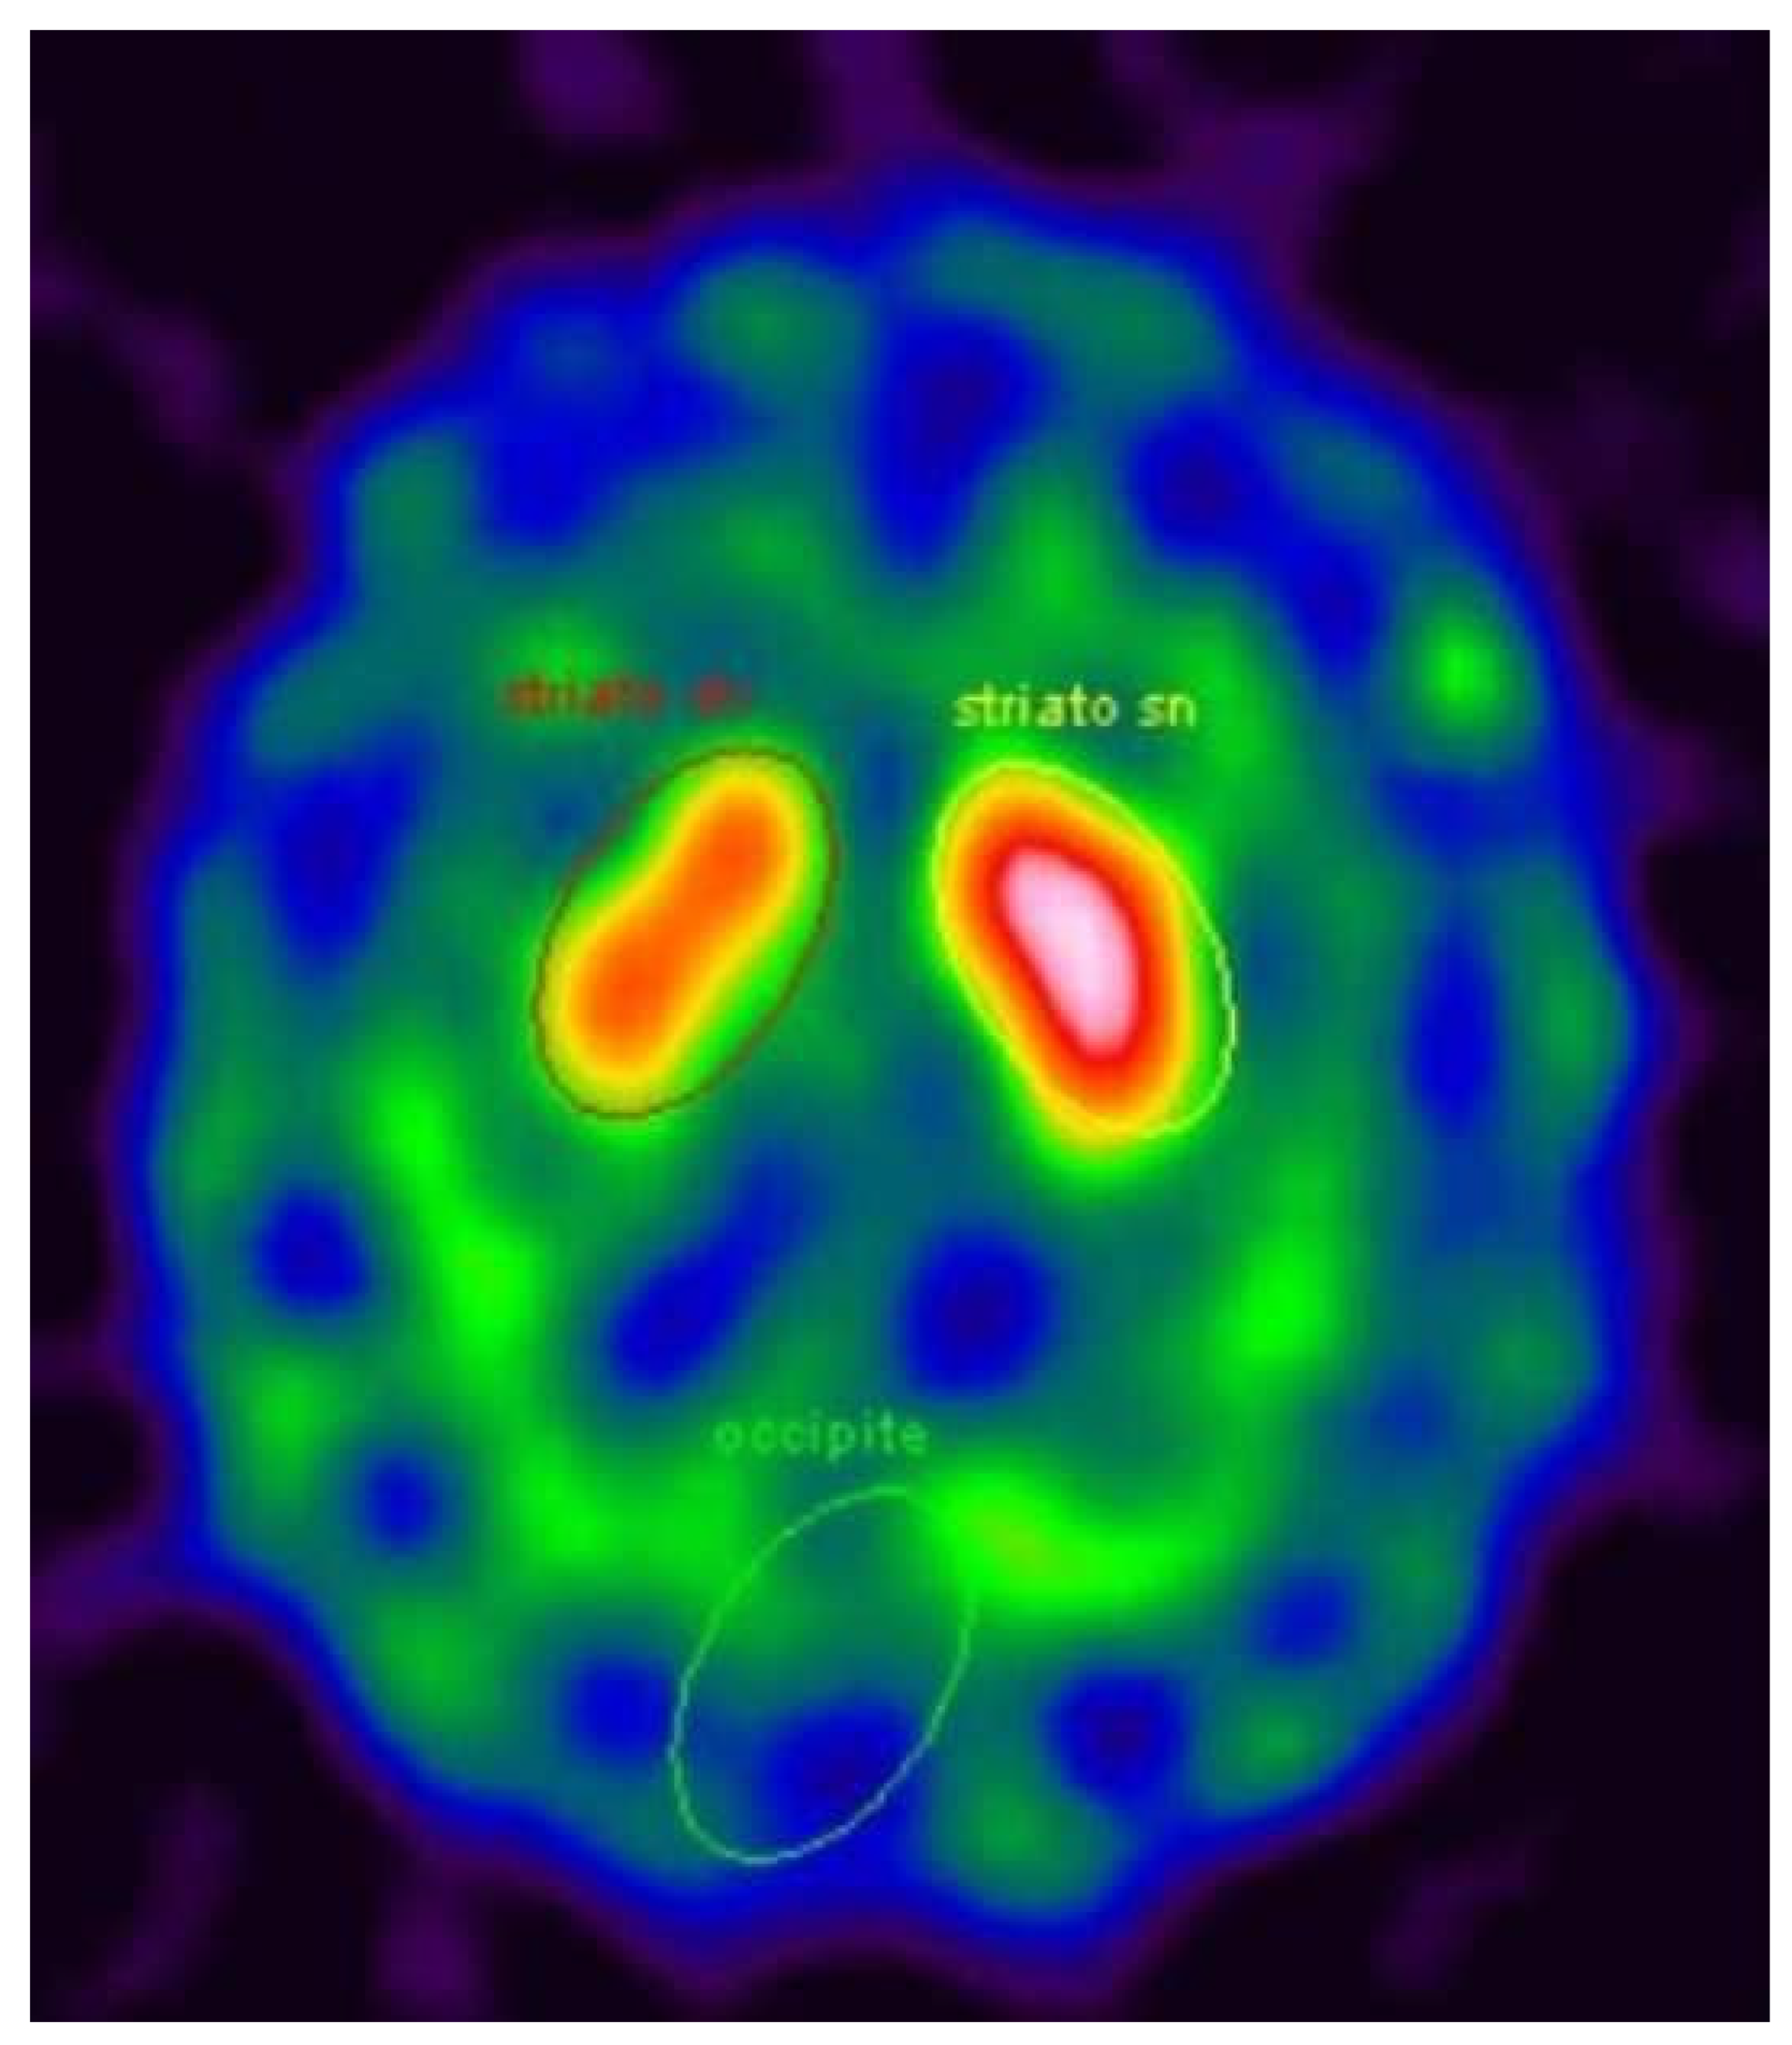

We aim to update the description of a patient monitored at the Neurology Department of Ferrara University that was published in 2010 [6]. He was a 69-year-old Caucasian male, with a long personal history of type II diabetes, hypertension, hypercholesterolemia, peripheral arterial obstruction, and depression (with a component of hypochondria) who worked in contact with glues and cement for about 40 years. The family history reported no neurological diseases. In 2007, the patient was referred to our centre complaining about severe headaches described as a “daily and increasingly strange sensation of pain in the head”, which was present every day and which had increased over time (started about 10 years earlier). The pharmacological medical history showed the use of clomipramine (for about 10 years), lorazepam, fluoxetine, delorazepam, oxazepam, and olanzapine (for about 1 year). Cognitive function, cranial nerve, and upper and lower limb functions were normal on neurological examination. Brain MRI disclosed a lesion in the pons compatible with myelinolysis. The actual reason why he presented this lesion was not clear, but in the case report, we discussed the possible role in the etiopathogenesis of his chronic use of anti-depressive drugs and the exposure to glue and chemical agents for 40 years [6]. Moreover, MRI showed signs of vascular encephalopathy, probably associated with his long history of hypertension and type II diabetes. After 4 years, at the age of 71, asymmetric signs of parkinsonism (rigidity and bradykinesia in the left hemibody) were found during clinical evaluation, so therapy with levodopa/carbidopa was started and the symptoms improved. A DaT-Scan SPECT revealed a moderate asymmetric reduction of pre-synaptic dopamine transporters in the right striatum (Figure 1).

Figure 1. DaT-Scan SPECT showing asymmetric reduction of dopamine transporters in right striatum.